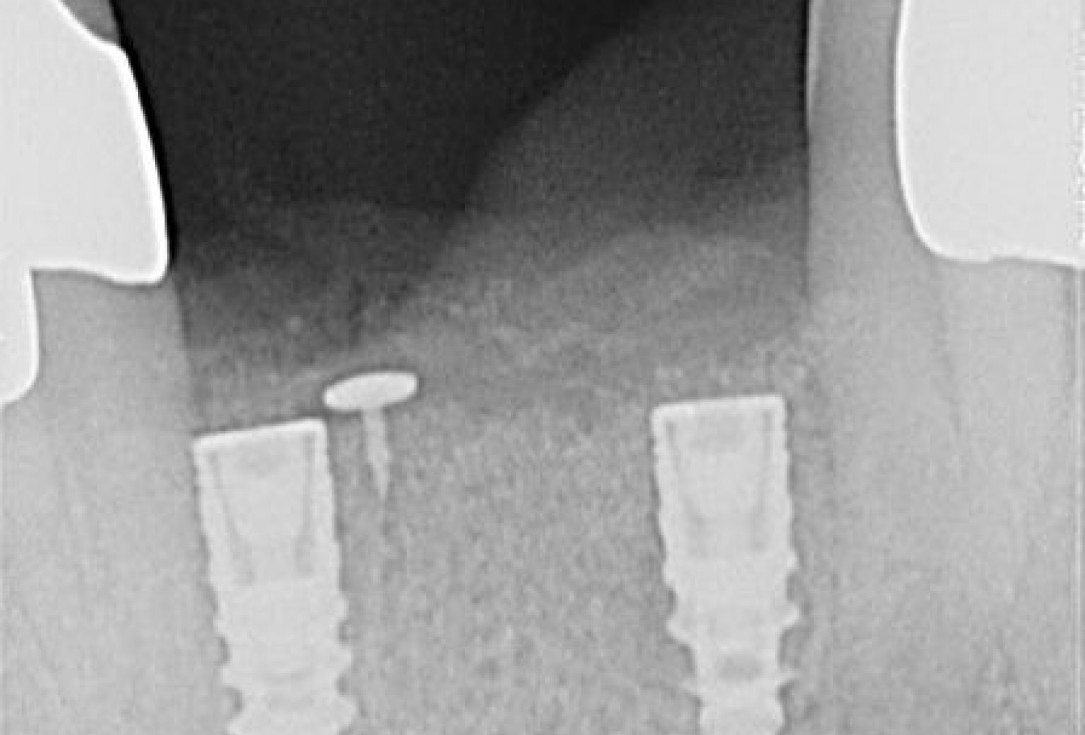

4/15 - Implants placed in the correct positionSoft tissue augmentation and GBR with mucoderm® and maxresorb® - Dr. S. Scherg